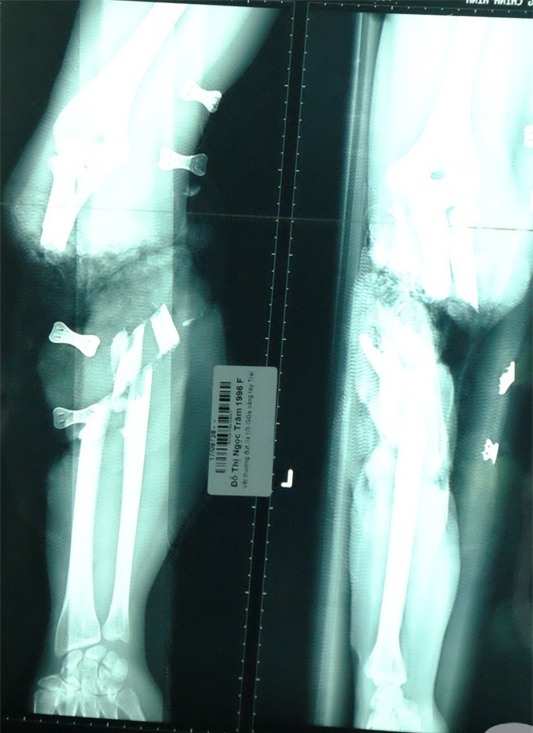

Ảnh siêu âm cho thấy 1/3 cánh tay bé trai bị đứt rời. |

BS Võ Hòa Khánh, BV Chấn thương Chỉnh hình TP HCM cho biết, khi nhập viện, cánh tay phải bệnh nhi đã trong tình trạng sưng đau, đầu chi nhạt, mạch quay khó bắt, các ngón tay không cử động được. Vì tình trạng quá nặng, các bác sĩ buộc phải đoạn chi 1/3 cánh tay phải để giữ tính mạng cho đứa bé.